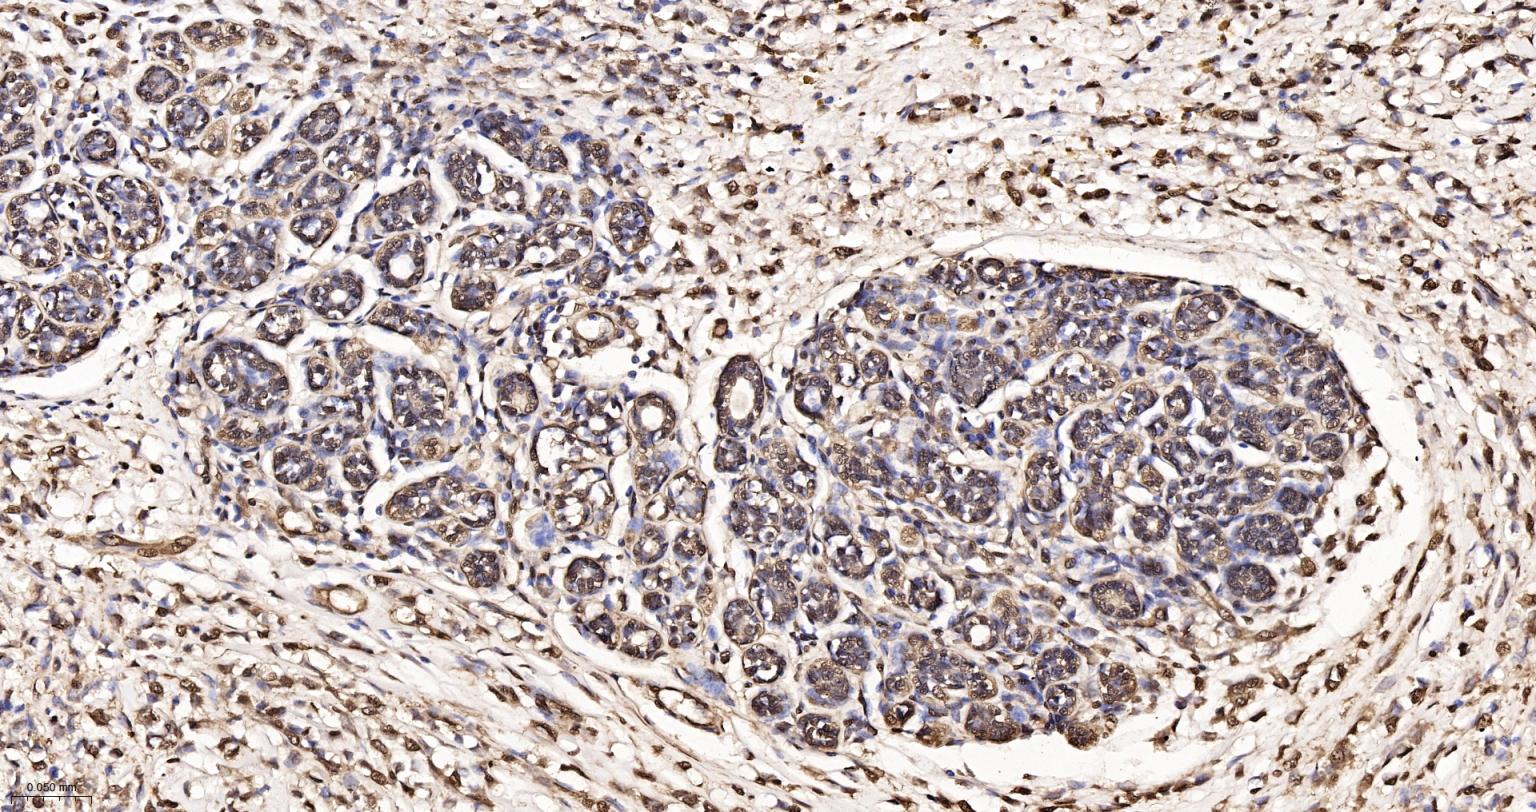

Paraformaldehyde-fixed, paraffin embedded Human Breast Cancer; Antigen retrieval by boiling in sodium citrate buffer (pH6.0) for 15 min; Antibody incubation with GAPDH Monoclonal Antibody, Unconjugated(bsm-52262R) at 1:250 overnight at 4°C, followed by conjugation to the SP Kit (Rabbit, SP-0023) and DAB (C-0010) staining.